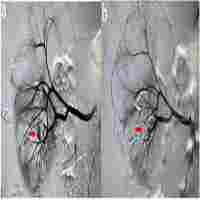

| Abstract | Background Accessory renal artery (ARA) is the most common site for anatomical variation of renal supply artery. Rare studies reported interventional embolization for the management of massive hemorrhage caused by ARA injury after percutaneous kidney biopsy (PKB). Case presentation We describe a 35-year-old man who developed massive hemorrhage after PKB leading to shock. Digital subtraction angiography (DSA) showed hemorrhage in the ARA at the inferior pole of the right kidney and hemostasis was noticed after renal artery embolization. Conclusions We proposed that much attention should be paid to the presence of ARA before PKB. In addition, digital subtraction angiography combined with superselective embolization is the best choice for the treatment of renal artery injury. |